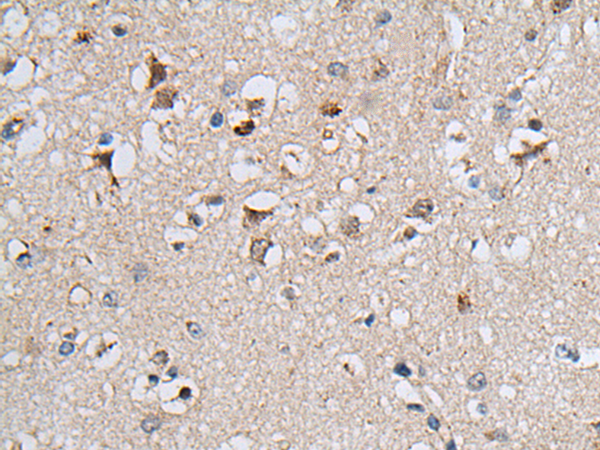

ELISA, IHC |

IHC positive control: |

Human colorectal cancer and human brain |

IHC Recommend dilution: |

25-100 |